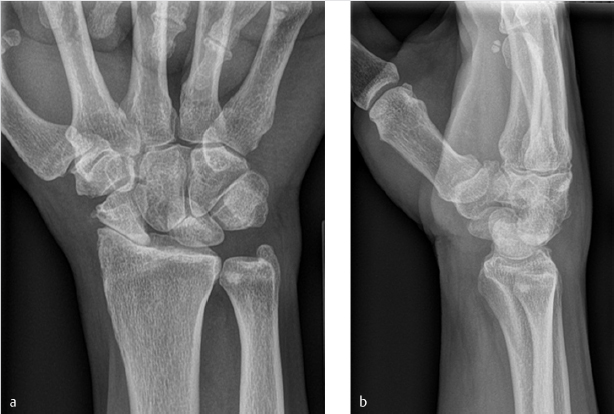

Plain radiographs: PA, lateral, ulnar deviation, and clenched fist views are usually sufficient for diagnosis and may reveal excessive flexion of scaphoid, scapholunate widening, and radiocarpal and/or midcarpal arthritis (► Fig. 59.1). We often obtain views of the contralateral wrist for comparison. When the condition of the radiolunate joint is unclear, magnetic resonance imaging (MRI), computed tomography (CT), or diagnostic wrist arthroscopy can be helpful.